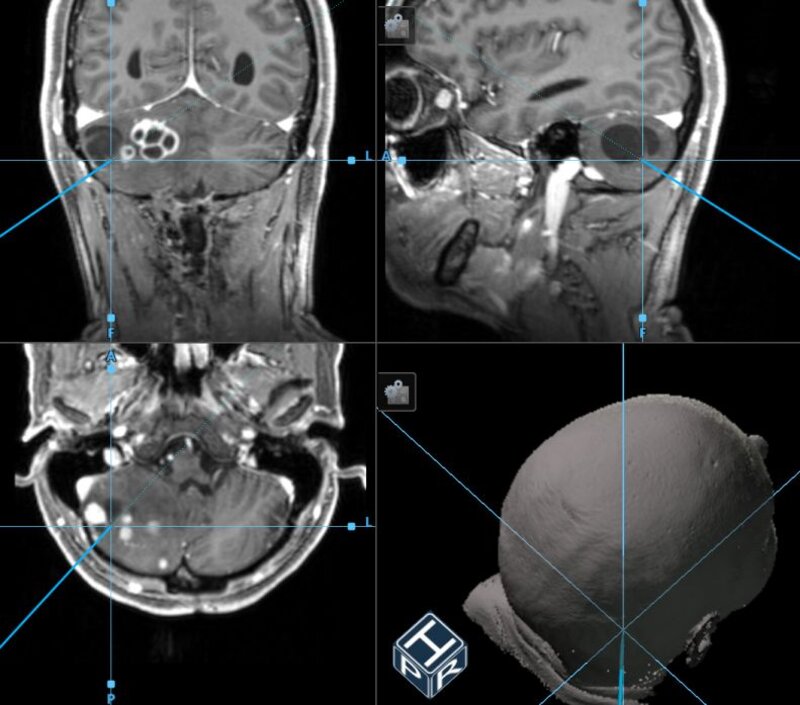

Intraoperative Neuronavigation: Unter Verwendung der intraoperativen Neuronavigation kann jeder beliebige Punkt hochpräzise im 3D Kernspintomographie (MRT)-Datensatz lokalisiert werden. Die Neuronavigation ist somit sowohl für die Planung des operativen Zugangsweges als auch für die gezielte Lagebestimmung von Hämangioblastomen oder deren Zysten von Vorteil.